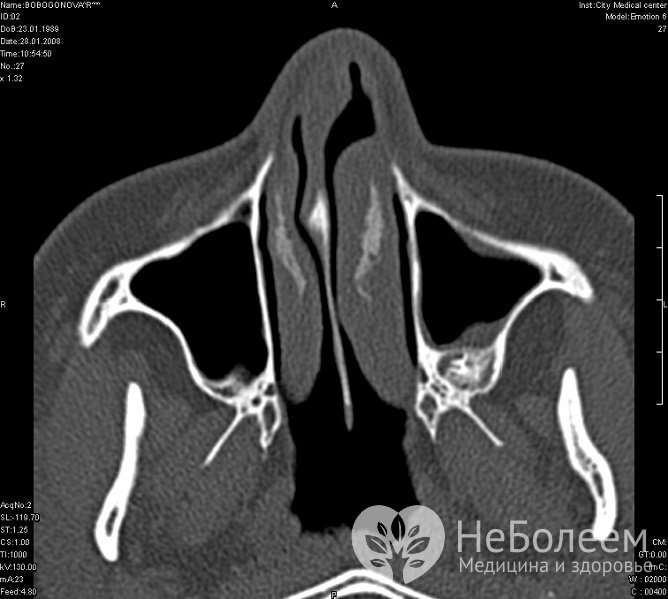

Врач устанавливает диагноз на основании клинической картины. К дополнительным методам исследования относится рентген околоносовых пазух в двух проекциях. Наиболее информативной является компьютерная томография.